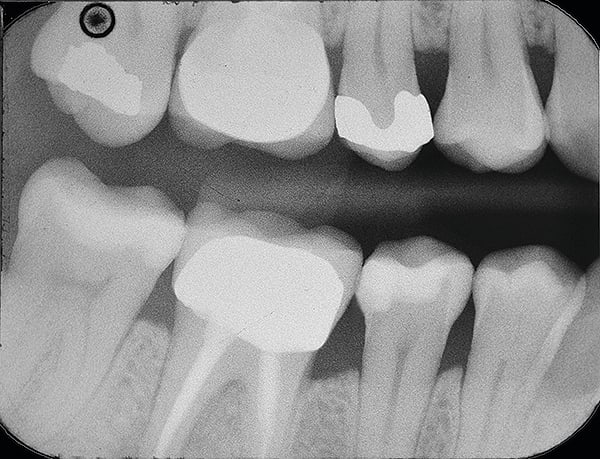

1. (Case 1) Preoperative view of tooth No. 29. Upon clinical examination, caries on the disto-occlusal was noted; a bitewing radiograph confirmed the need for an interproximal restoration.

10. Final radiograph of the disto-occlusal restoration on tooth No. 29 showing excellent contour, marginal adaptation, and radiopacity. Note that the radiopacities of SureFil® SDR® flow material and TPH Spectra® composite were matched to create the appearance of one contiguous restoration without demarcations between material layers.